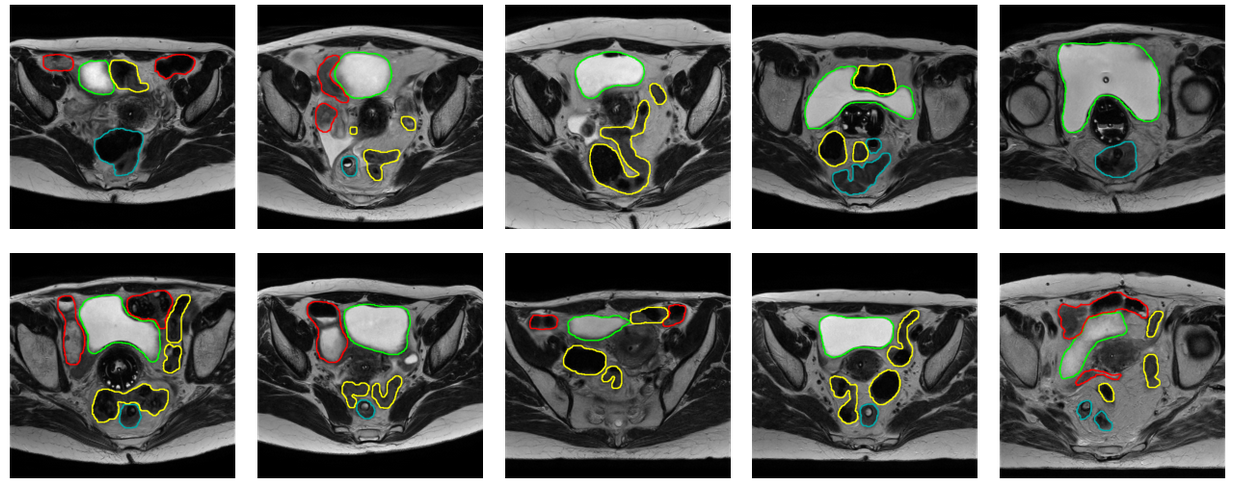

Refer to caption

Figure 6: Slices of images from the Cervical Cancer Dataset. Green: bladder, Red: bowel, Cyan: rectum, Yellow: sigmoid.

For visualization purposes, we calculate the average Dice Coefficient of every model, for every round in their 5-fold experiment, resulting in 5 scores per model. Then we average all these values for every fold, resulting in 5 final values. We sort them, and keep the fold that corresponds to the median of these values, which in our case was the 2ndsuperscript2𝑛𝑑2^{nd} fold. We randomly selected 4 patients from the validation set of this fold, from which we then selected 1 slice from each patient based on the reference that contains a lot of information. The results are presented in Figure 7 and Figure 8.

Figure 7: Predictions of models on the Cervical Cancer Dataset. Green: bladder, Red: bowel, Cyan: rectum, Yellow: sigmoid.